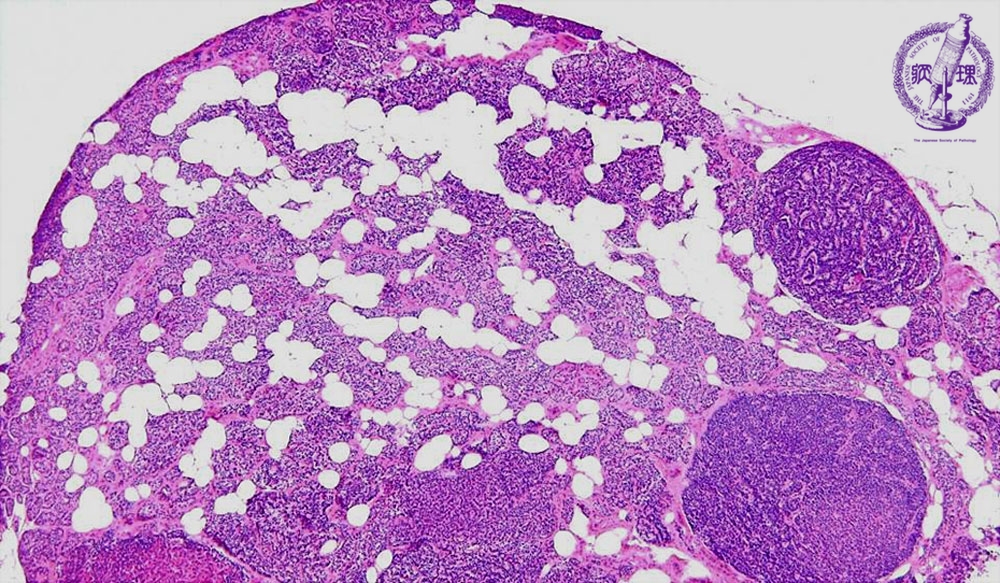

Microscopic findings (HE stain, low power view). Secondary parathyroid hyperplasia in a patient on long-term hemodialysis. Multiple micro-nodules (arrows) and adipose tissue are apparent in the enlarged parathyroid gland.